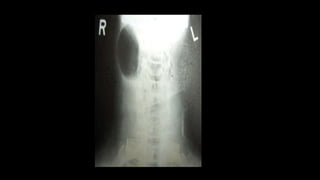

LARYNGOCELE

•A laryngocele is an air filled cystic dilatation of the

saccule or appendix of the ventricle.

•It occurs in people with congenitally large ventricular

appendix.

•It is predisposed by activities which increase the

intralaryngeal pressure, like straining (weight lifters),

glass blowers and trumpet players

Pathological types:

•External-swelling lateral to thyrohyoid membrane

•Internal-swelling of false cords and aryepiglottic folds

•Combined/Mixed

•Symptoms:

•Internal & Mixed: Hoarseness and cough. Stridor if

large.

•External: Compressible mass in the neck, that

increases on coughing or Valsalva manoeuvre.

•Bryce’s sign: Gurgling and hissing sound when the

neck mass is compressed.

•Investigations: X-Ray during Valsalva, CT scan,

Laryngoscopy to rule out malignancy

TREATMENT:

•External/mixed:

Transcervical neck

dissection with

removal of part of

thyroid lamina.

•Excision of the cyst

or marsupialisation